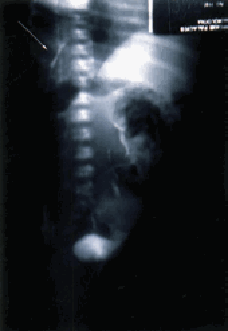

Figura 3. Representa una sección sagital izquierda del tronco donde se observa un defecto diafragmático posterolateral y riñón izquierdo dentro de la cavidad torácica y dentro de la cavidad pleural.

a. En la primera, el riñón es parte del contenido herniario, está localizado dentro de la cavidad pleural y puede ser movilizado de la cavidad torácica a la abdominal. Los casos reportados por Gordils y col.

(5), Ho y col. (7), Hallisey y Caride (35) pertenecen a esta variedad.b. En la segunda, el riñón está dentro de la cavidad torácica pero por fuera de la cavidad pleural (Figura 2), y no forma parte del contenido herniario. Cuando el contenido herniario es reducido, el riñón torácico se muestra a través de la pleura parietal posterior como masa sólida intratorácica de forma arriñonada. El caso reportado aquí por nosotros pertenece a esta variedad.